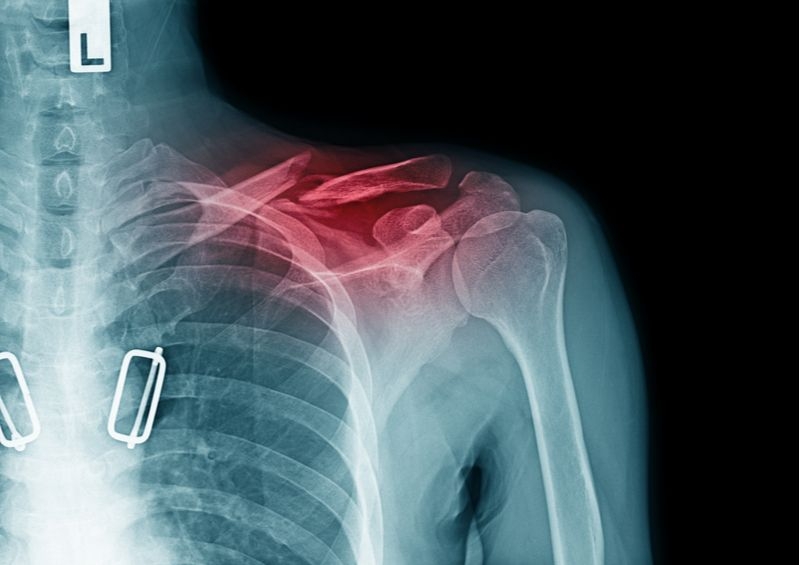

Khi đến bệnh viện, bác sĩ sẽ thực hiện một số biện pháp kiểm tra như là chụp X quang để xác định vị trí xương gãy, mức độ trật khớp (nếu có).

Đặc biệt, trường hợp trật khớp vai kèm theo gãy xương, bác sĩ sẽ chỉ định thực hiện kết hợp phương pháp chụp CT scan để tăng độ chính xác cho kết quả chẩn đoán. Ngược lại, nếu tình trạng trật khớp đơn thuần không bị gãy xương, bạn có thể được điều trị bằng những biện pháp không xâm lấn khác như nắn khớp, cố định vai hay sử dụng thuốc giảm đau, thuốc giãn cơ.

Chụp X-quang trật khớp vai Bị trật khớp vai khi ngủ là tình trạng tương đối phổ biến. Mặc dù không quá nguy hiểm nhưng nếu không chữa trị kịp thời có thể dẫn đến nhiều biến chứng khó lường. Vì vậy hãy lập tức đến gặp bác sĩ nếu nhận thấy tình trạng của mình có nhiều chuyển biến bất thường nhé!